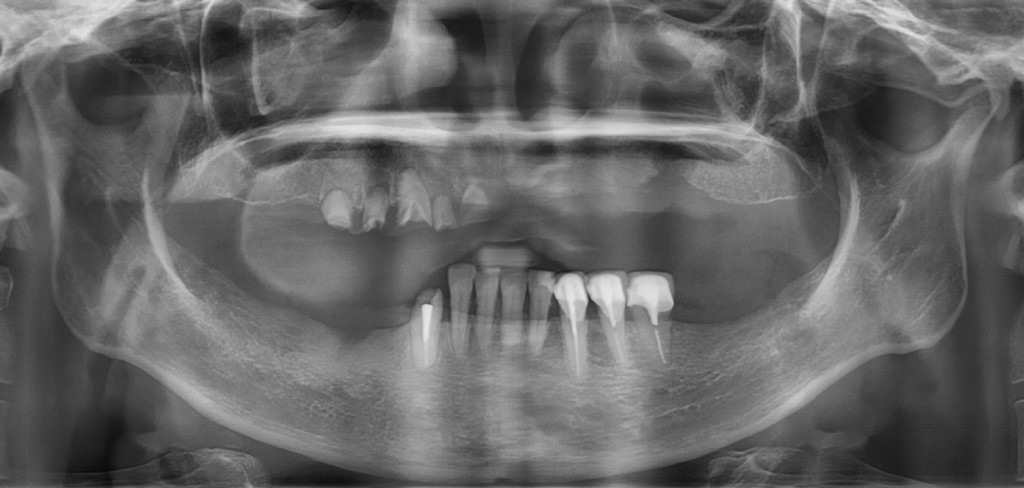

告別鬆動假牙與飲食限制。日出「全植牙」方案,結合 3D 數位導航與全瓷美學,為您重塑穩固咬合與年輕面容,讓每一天都像日出般充滿希望。

日出「全植牙」體系,專為全口缺牙或多顆缺牙者設計,擺脫傳統假牙易晃動、磨損齒槽骨的缺點,提供如同真牙般的咬合力與穩定度。

透過高解析 3D 電腦斷層與口腔掃描,在電腦中預先精算出最完美的植入點。利用數位導航板或動態追蹤技術,避開血管與神經,讓全口重建手術更安全、更透明。